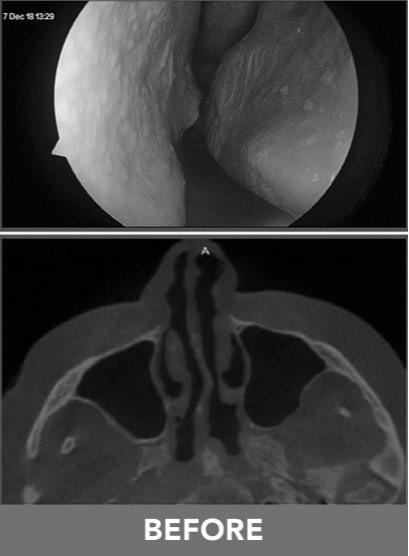

This is a minimally invasive procedure designed to relieve nasal airway obstruction (NAO). It works by gently opening the nasal passages with a small, inflatable balloon.

Nasal obstruction occurs when airflow through the nose is restricted, making it harder to breathe, especially during physical activity. Common symptoms include a stuffy or congested nose and difficulty breathing through the nose.

The RELIEVA TRACT® Nasal Balloon Dilation System is a state-of-the-art instrument designed to clear blockages and relieve symptoms of nasal airway obstruction. Below are the steps of what you can expect during your procedure: